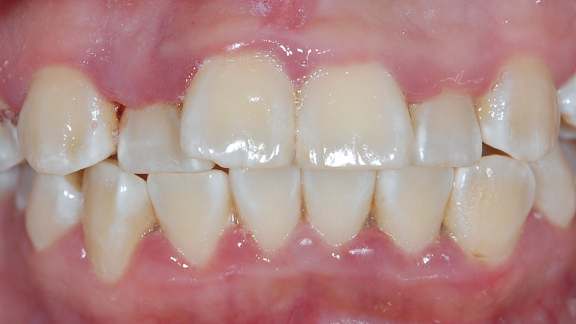

Orthodontics

Beautiful Smile

Understanding Early Orthodontic Assessment

Orthodontics is a recognized dental specialty that addresses issues related to the alignment of teeth and jaws. Early assessment may help identify developmental concerns such as spacing, crowding, or bite discrepancies.

The American Association of Orthodontists (AAO) recommends that children receive their first orthodontic evaluation by the age of 7. At this stage, a combination of primary and permanent teeth is present, allowing orthodontists to detect potential concerns early and provide appropriate guidance.

Early evaluations may support timely management of developing issues. Treatment options such as braces, jaw expanders, removable appliances or clear aligners may be considered based on individual clinical needs.